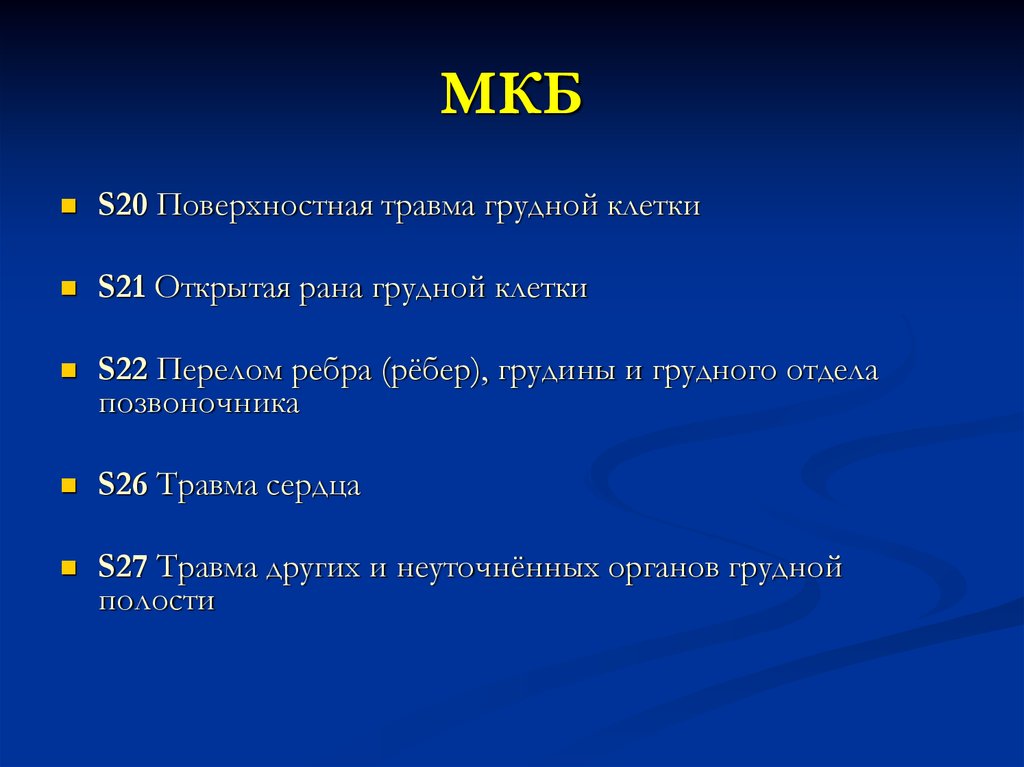

Код мкб 10 атерома головы

Код мкб 10 атерома головы 109 фото